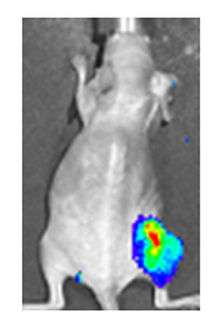

Viral luciferase expression in a mouse tumour

Both in the laboratory and in the clinic it is useful to have a simple means of identifying cells infected by the experimental virus. This can be done by equipping the virus with 'reporter genes' not normally present in viral genomes, which encode easily identifiable protein markers. One example of such proteins is GFP (Green fluorescent protein) which, when present in infected cells, will cause a fluorescent green light to be emitted when stimulated by blue light.[70][71] An advantage of this method is that it can be used on live cells and in patients with superficial infected lesions, it enables rapid non-invasive confirmation of viral infection.[72] Another example of a visual marker useful in living cells is luciferase, an enzyme from the firefly which in the presence of luciferin, emits light detectable by specialized cameras.[70]